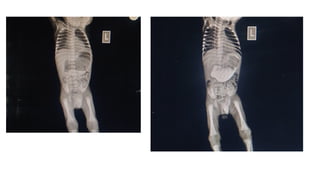

14 DAYS MALE BABY OF BHAVANI

14 DAYS MALEBABY OF BHAVANI